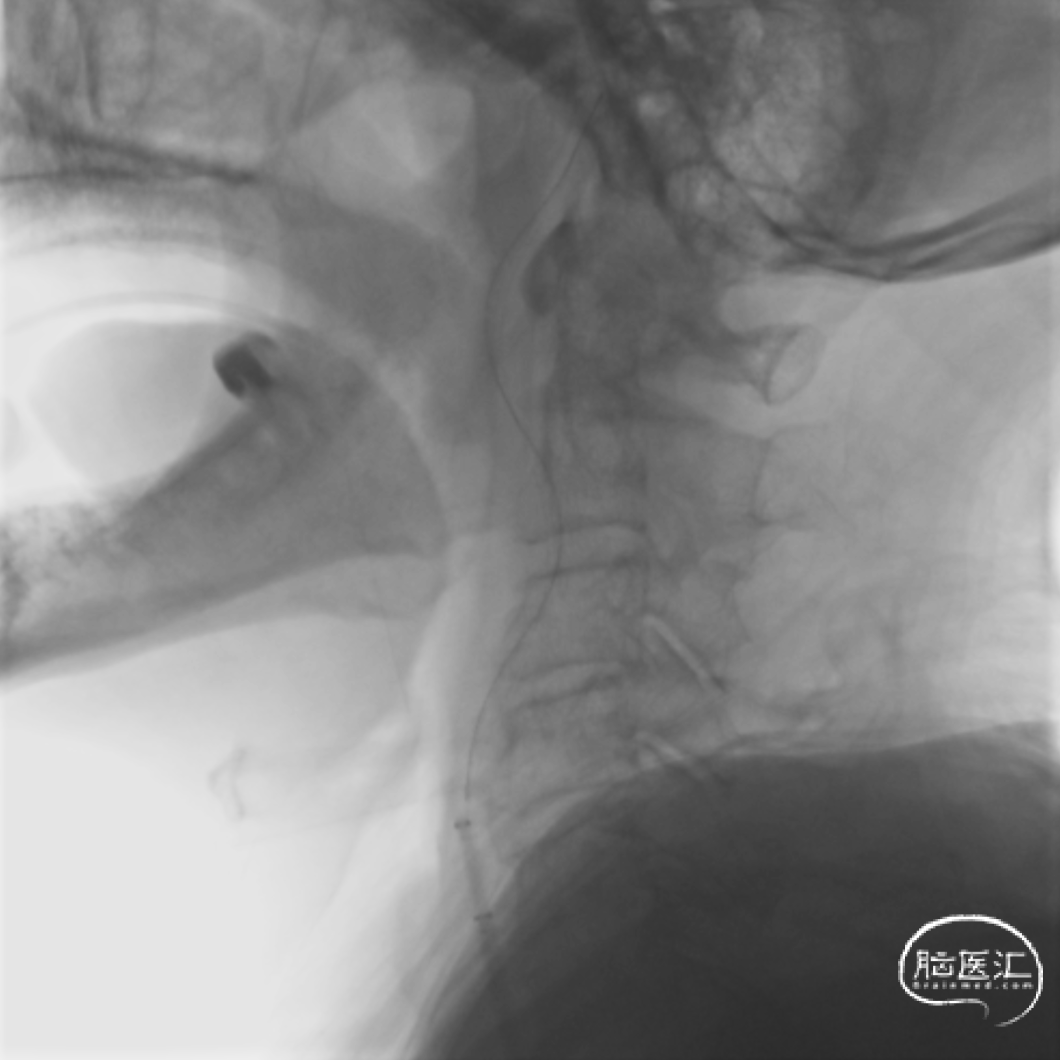

FlowGate 2同轴Catalyst 7、Synchro 2多次调整后穿过C1起始闭塞处,MicroPort Pioneer 2.5mm×20mm球囊C1起始处缓慢扩张,顺球囊Catalyst 7穿过闭塞段,继续向前推进FlowGate 2失败, Catalyst 7 C1抽吸出长条血栓。

Catalyst 7 C1抽吸出大负荷血栓。

Catalyst 7再次通过闭塞处于C2-C4近端抽吸,再无血栓抽出,球囊辅助通过(BTA)技术无法将CAT7带入C4远端,CAT减容任务完成,使用Solitaire FR 6×30支架行完整BADDASS技术, 6×30支架前行张力非常大,释放时并无法顺利推出Rebar 18微导管,导致支架释放略近于预期位置。

支架释放位置不理想,而且前行过程中导致血栓前移,支架并未覆盖血栓头端,经验告诉我们,仅靠软膜支的独立系统可能会通过BGC的血流阻断弥补前向压力(P),远端未覆盖血栓可能会因为血栓之间的粘附力而一并拖出。

充盈FlowGate 2,CAT 7施加张力,希望CAT 7能在支架回撤过程中抓住血栓尾端,但CAT 7在虹吸弯纹丝不动,负压下同时撤出支架与DAC。

BADDASS技术下支架取出长条血栓,3D-DSA可见眼动脉下方重度狭窄,CAT 7在张力下的上行切割狭窄处,导致小夹层产生。